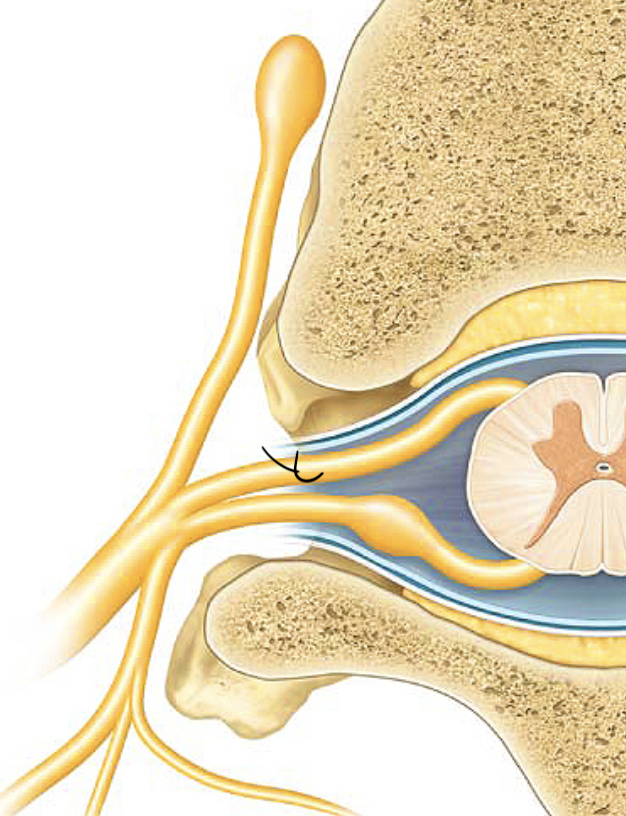

meninges

three layers of connective tissue in which the brain and spinal cord are wrapped/ The WHOLE LAYER

epidural space

The yellow stuff on TOP Cushion of fat and network of veins in space between vertebrae and spinal dura mater

dura mater

pink layer

arachnoid mater

the light blue layer

subarachnoid space

The spaces between the purple/ The blue

pia mater

The first top layer/ under the purple stuff

dorsal root

the sensory branch of each spinal nerve

dorsal root ganglion

contains cell bodies of sensory neurons

ventral root

the basal branch of each spinal nerve; carries motor neurons

spinal nerve

a peripheral nerve attached to the spinal cord. Motor and Sensor nerve.

rami

branches of spinal nerves

dorsal ramus

the division of posterior spinal nerves that transmit motor impulses to the posterior trunk muscles and relay sensory impulses from the skin of the back

ventral ramus

gray rami communicantes

Carry unmyelinated postganglionic sympathetic axons from trunk to all spinal nerves

sympathetic trunk

nerve running along each side of the vertebral column

sympathetic trunk ganglia

big yellow thing